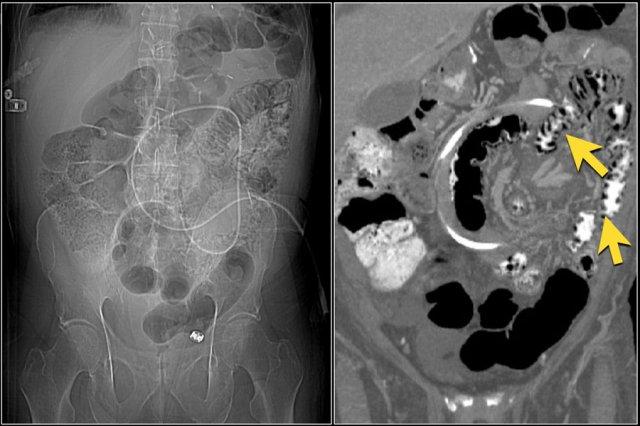

Đây là một bệnh nhân khác bị thiếu máu cục bộ một đoạn dài ruột non do tắc ruột quai kín.

Một đặc điểm hình ảnh quan trọng của tắc ruột quai kín là hình ảnh các quai ruột non giãn xếp theo kiểu nan hoa bánh xe với các mạch máu mạc treo hội tụ về một điểm trung tâm.

Các dấu hiệu thiếu máu cục bộ trong tắc ruột quai kín tương tự như ở các bệnh nhân có nguyên nhân thiếu máu cục bộ mạc treo khác:

- Dày thành ruột

- Phù nề mạc treo ruột

- Cổ trướng

- Sự ngấm thuốc của thành ruột trong thiếu máu cục bộ có thể bình thường, tăng do hiện tượng tái tưới máu, hoặc giảm/mất ngấm thuốc như trong trường hợp này.